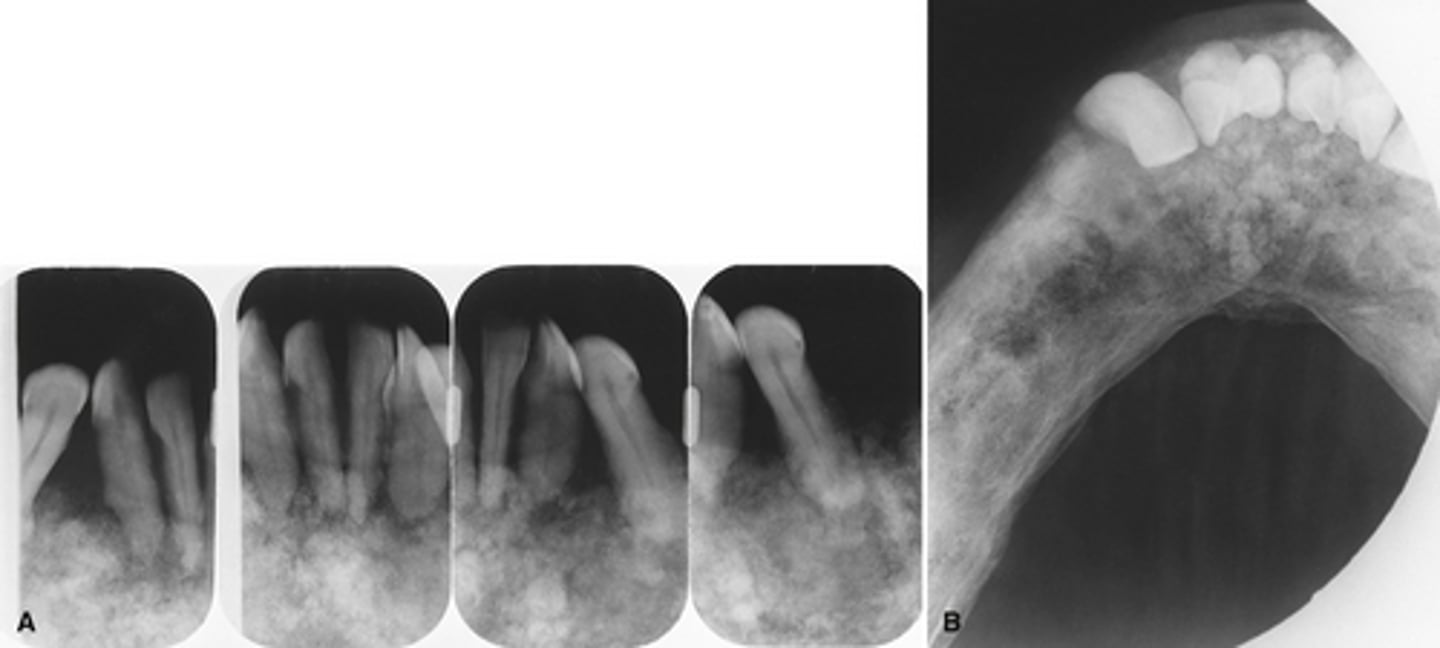

[periapical] Cemento-osseus dysplasia (PCOD)-

PCOD- Most common location anterior mandible

PCOD - Developing- Mature stage

PCOD- Mature stage

PCOD through its stages from Early ---> developing ---> Mature

PCOD will have a radiolucent rim and will also have loss of the lamina dura around the teeth involved

How can you differentiate the mature stage PCOD from dense bone island?